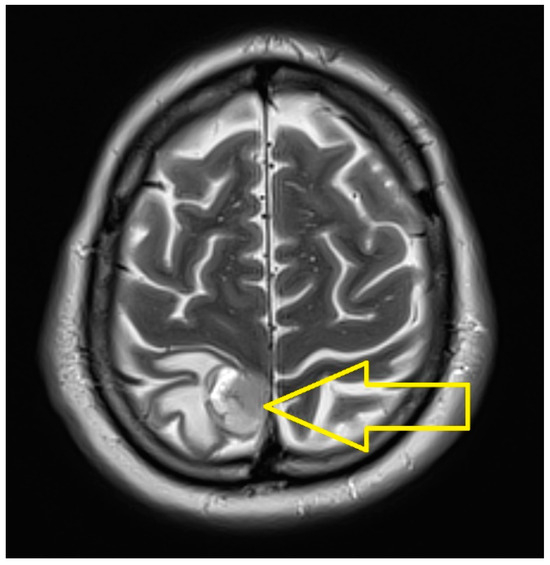

2. Case Presentation